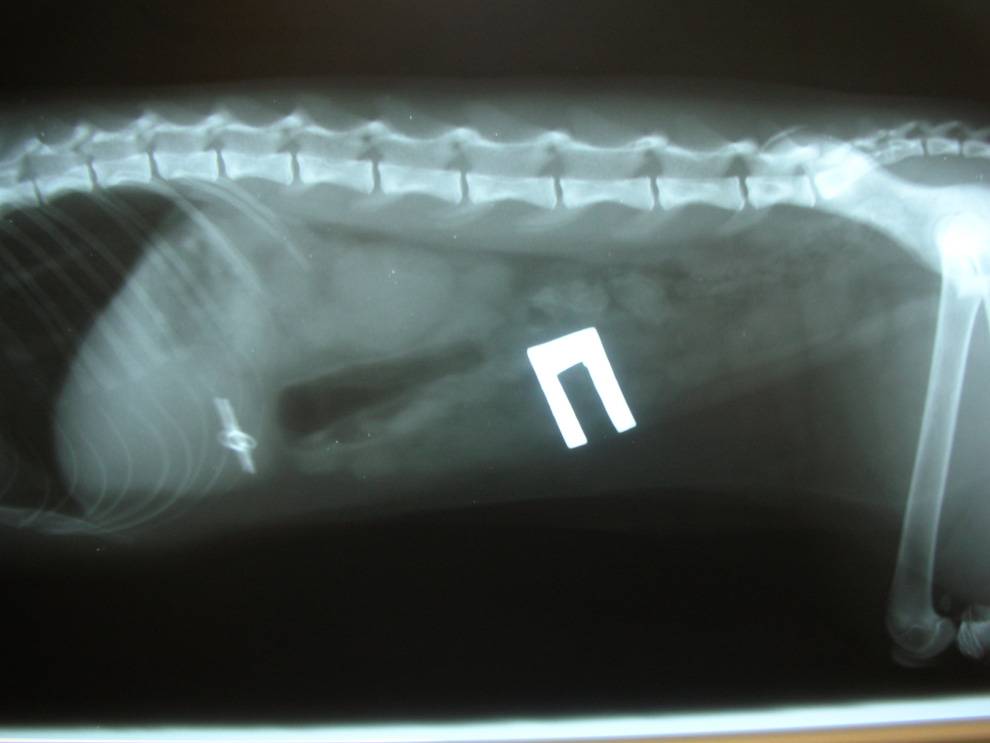

При посещении клиники ветеринар сначала осматривает собаку. Сразу обнаружить инородное тело можно, если оно застряло в глотке. Если проглочен крупный и твердый предмет, его можно нащупать при пальпации брюшной полости. В остальных случаях применяется инструментальная диагностика.

- Рентгенография поможет выявить наличие металлических, резиновых предметов, камней. На рентгене также видна деформация и другие изменения в органах пищеварительного тракта, характерные для присутствия инородного тела.

- Чтобы точно определить место предмета и проследить его продвижение по пищеварительному тракту, делается рентген с контрастным веществом. Чаще используется барий.

- Ультразвуковое исследование поможет определить наличие любого инородного тела. На УЗИ видно, если кишечник закупорен.

- Эндоскопия – самый информативный метод обследования. Он подтвердит наличие постороннего предмета в пищеварительном тракте и поможет оценить состояние слизистой.